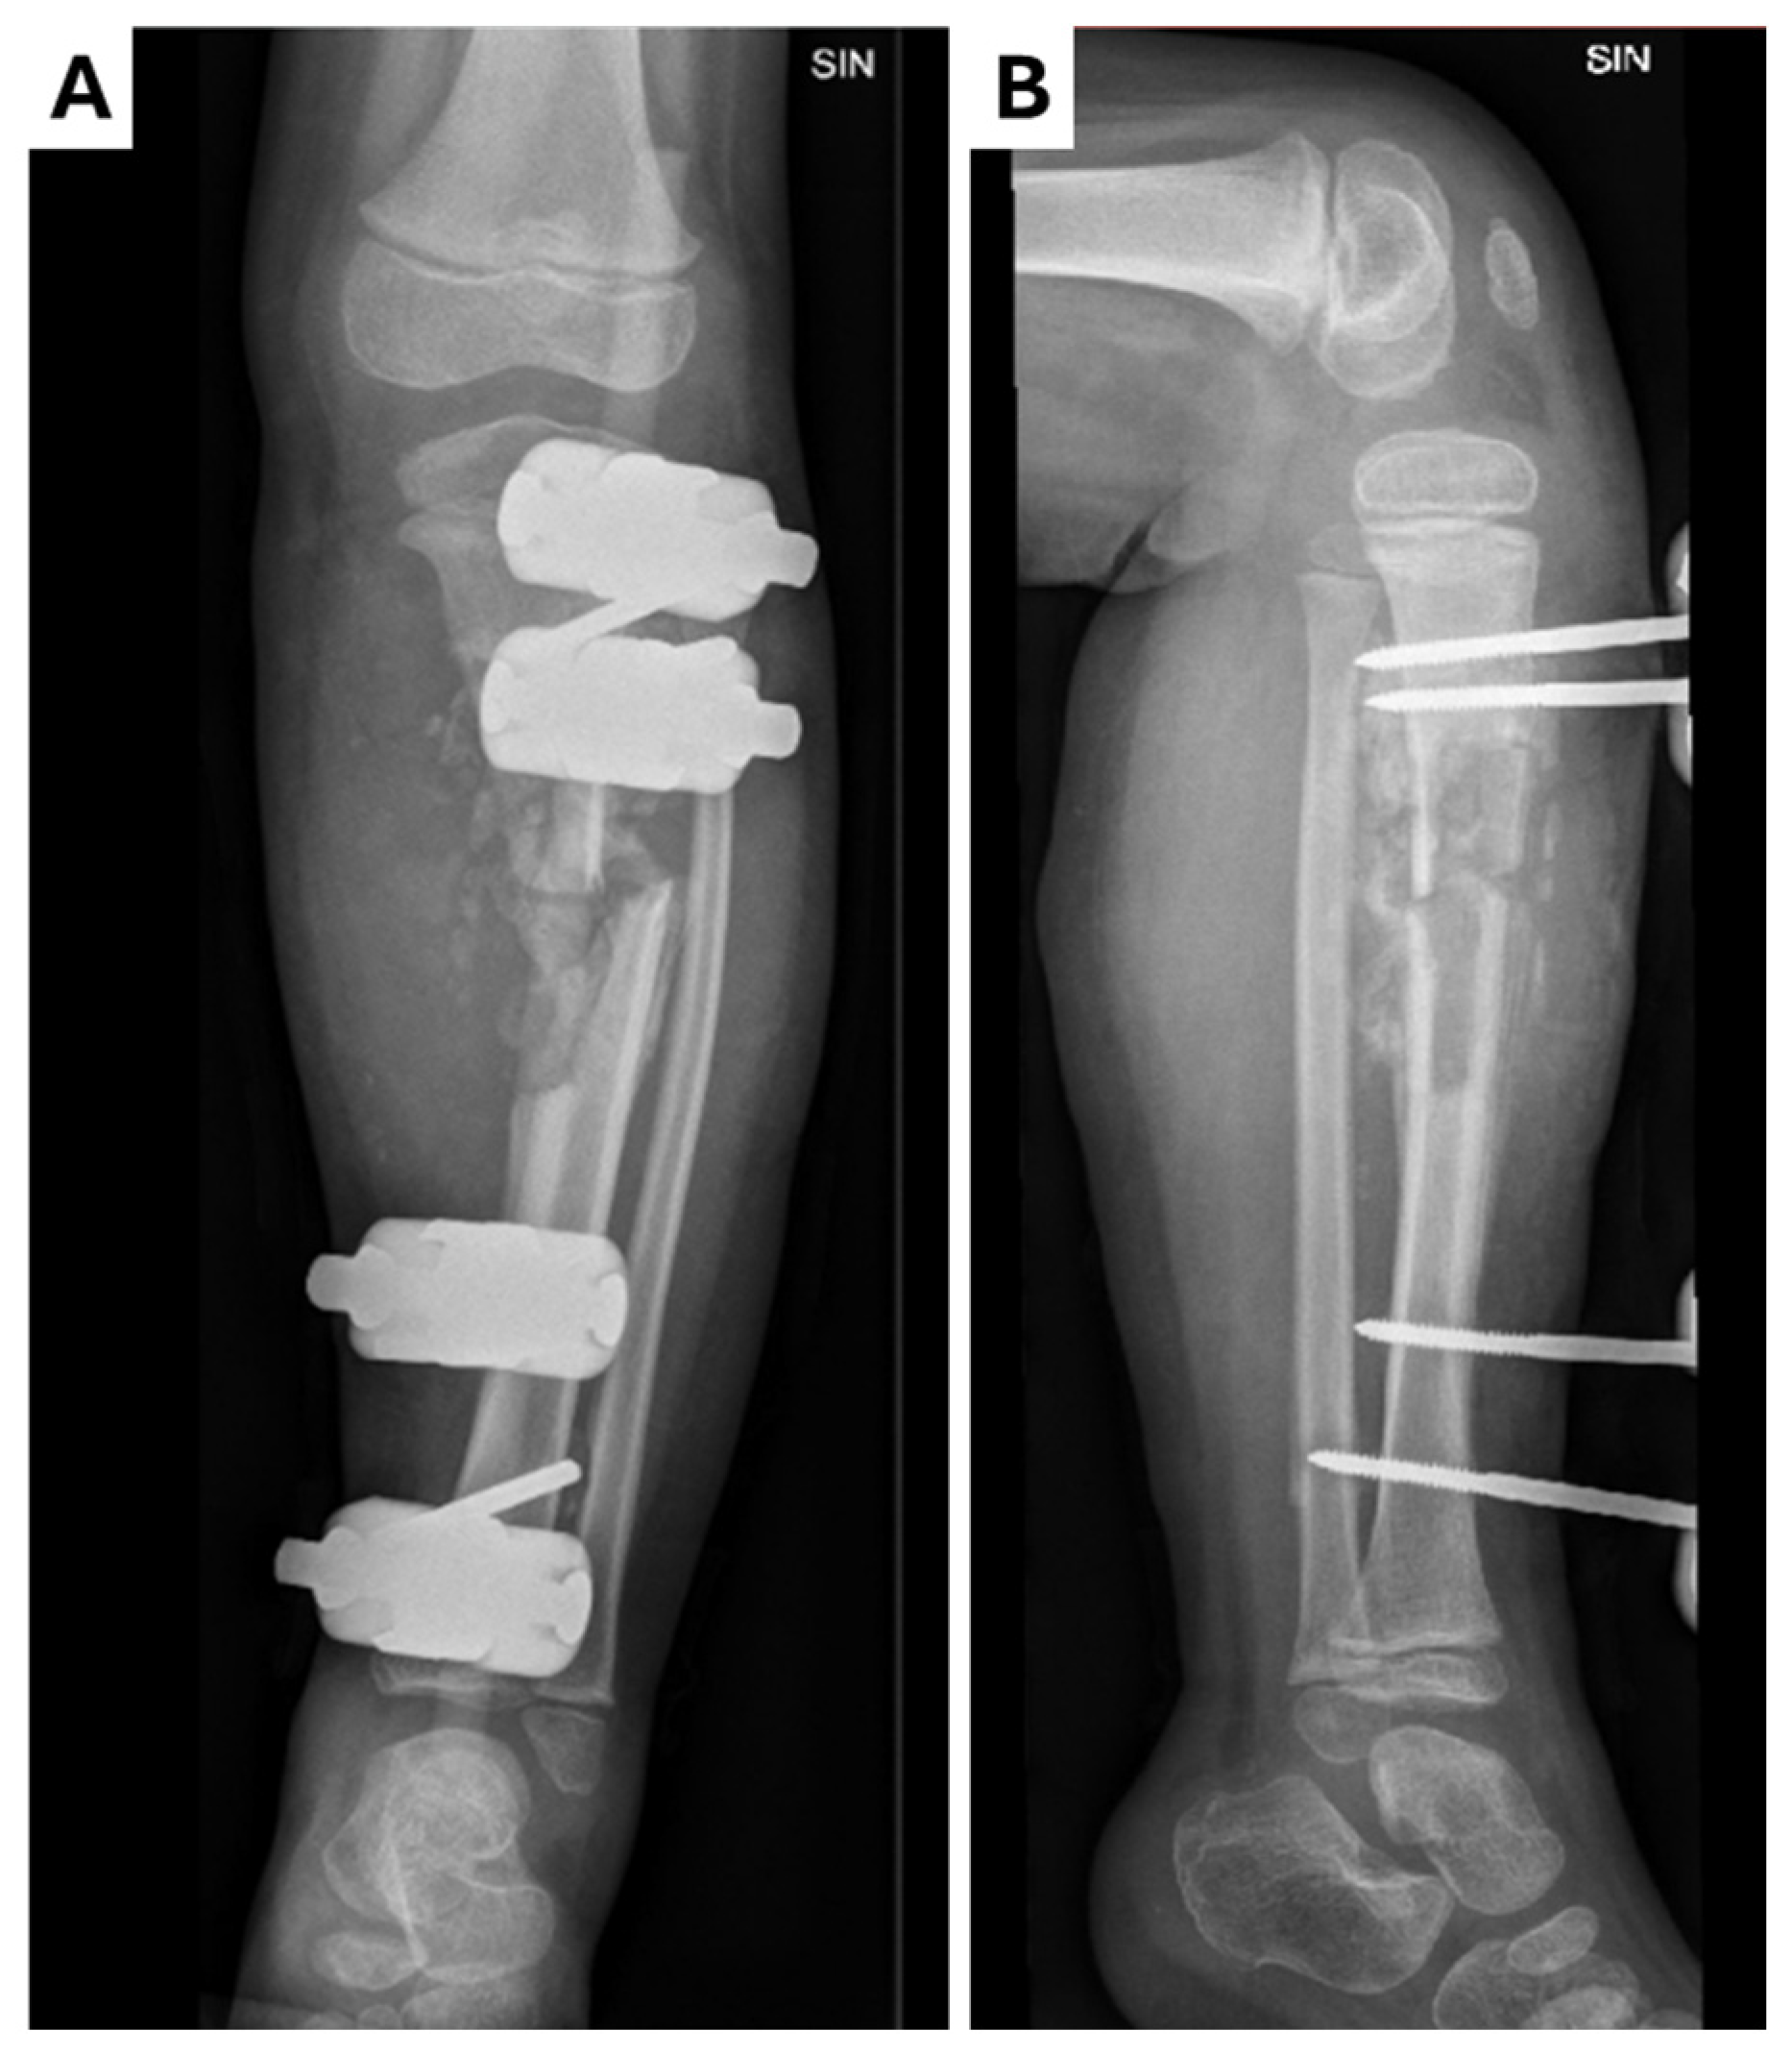

2.5. Fourth Hospitalization at the Children’s Clinical University Hospital (CCUH)

2.6. Fifth Hospitalization at the Children’s Clinical University Hospital (CCUH)